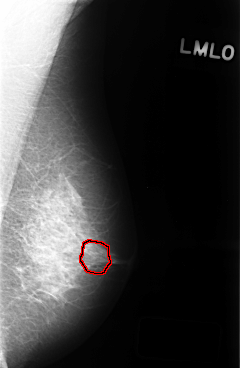

C_0320_1.LEFT_MLO

LEFT_MLO LINES 4416 PIXELS_PER_LINE 2880 BITS_PER_PIXEL 12 RESOLUTION 50 OVERLAY

FILE: C_0320_1.LEFT_MLO.OVERLAY

TOTAL_ABNORMALITIES 1

ABNORMALITY 1

LESION_TYPE CALCIFICATION TYPE PUNCTATE DISTRIBUTION CLUSTERED

ASSESSMENT 4

SUBTLETY 3

PATHOLOGY BENIGN

TOTAL_OUTLINES 1

BOUNDARY